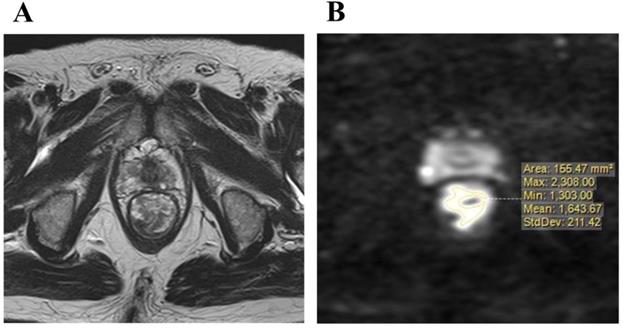

Imaging was performed with a 1.5 or 3.0 T pelvic MRI with pelvic phased-array coils at KPUM or related medical centers. T2-weighted axial images with a section thickness of 5-7 mm and sagittal images with fast spin-echo sequences were acquired. An axial diffusion-weighted sequence with background body signal suppression (DWIBS, b-values 800-1000 s/mm2) was also obtained. Primary resection cases underwent MRI for staging before surgery, and pCRT cases for pre-treatment staging and re-staging in order to diagnose therapeutic responses almost 4 to 7 weeks after the completion of pCRT. DWI were evaluated for the maximum cut surface of an axial image of the rectal tumor, which was identified by a T2-weighted axial image. Areas of a higher signal intensity than the normal bowel wall or background on DWI were considered to be the primary tumor. The distribution of signal intensity in this high-intensity area was evaluated, and then maximum (MAX) and minimum (MIN) value of signal intensity in tumor were measured (Figure 2A, B). Furthermore, the intra-tumor heterogeneity of the signal intensity on DWI was quantified using the following formula.

Figure 2

A: T2-weighted axial image of the maximum cut surface of lower rectal carcinoma, B: The distribution signal intensity on a diffusion-weighted image in the maximum cut surface was measured.

HSD = [(MAX value of signal intensity) - (MIN value of signal intensity)] / [(MAX value of signal intensity) + (MIN value of signal intensity)].